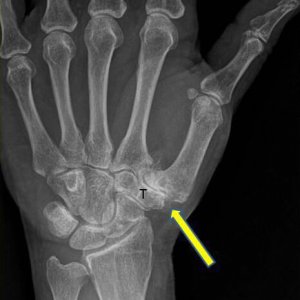

Präoperativ: Deutliche Arthrosezeichen am Gelenkspalt zwischen dem Handwurzelknochen (T) und dem Daumen (Pfeil)